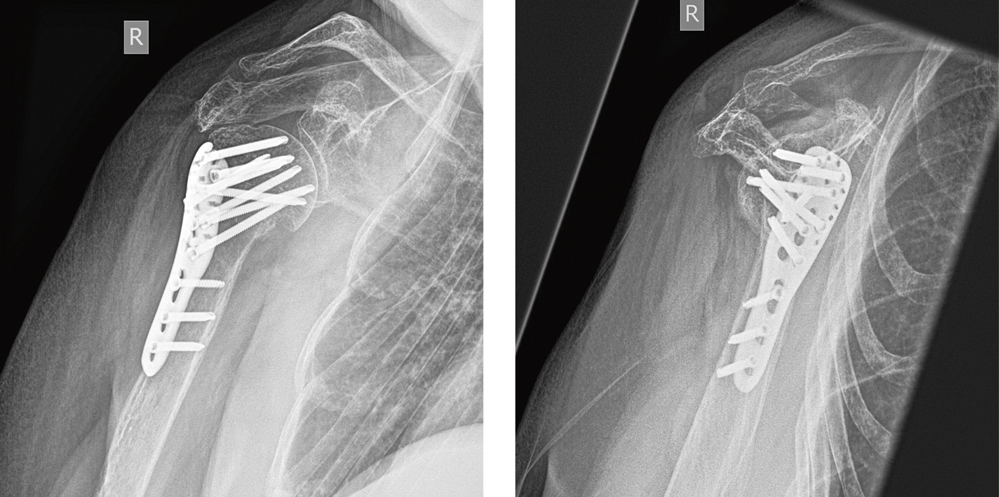

Bei subjektiver Beschwerdeprogredienz entschied sich die Patientin dann für eine operative Therapie. Am Folgetag wurde die Fraktur osteosynthetisch mittels winkelstabiler Platte versorgt (Abbildung 9).

Abbildung 9: Patientin B – Postoperative Röntgenaufnahme nach osteosynthetischer Versorgung mittels winkelstabiler Platte.

Gleich postoperativ konnte mit intensiver passiver sowie aktiver Physiotherapie begonnen werden. Nach sechs Wochen zeigte sich das funktionelle Ergebnis mit schmerzfreier 90° Abduktion und 90° Anteversion, vergleichbar gut wie bei Patientin A.